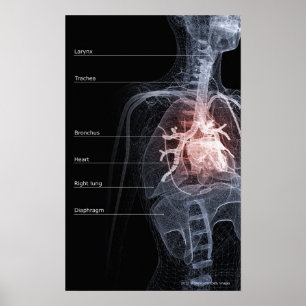

Diagram över andningssystemet och hjärtat vykort

Pris21,00 kr

Diagram över andningssystemet och hjärtat poster

Pris343,00 kr